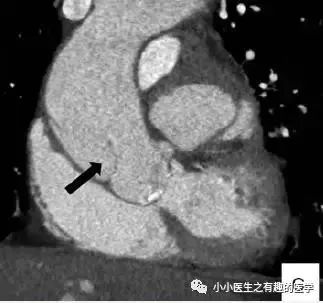

足球王国巴西报道的一例。

这是什么?

病理:Intimal sarcoma of the pulmonary artery,肺动脉内膜肉瘤。

仔细看看:

CT示肺动脉内肿块,肿块侵犯纵隔,血栓不会跑到纵隔。